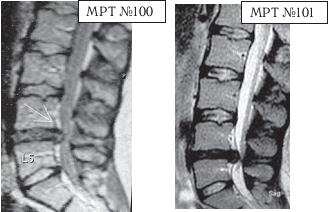

МРТ № 1

На магнитно-резонансной томографии (МРТ) № 1 — шейный отдел позвоночника, в относительно нормальном состоянии.

Шейный отдел позвоночника должен иметь нормально выраженный физиологический лордоз, не должно быть гиполордоза или гиперлордоза, а так же кифотических деформаций.

Ширина спинного мозга: сагиттально > 6–7 мм

1. Сагиттальный размер позвоночного канала на уровне:

СI 21 мм

СII 20 мм

СIII 17 мм

CIV-CVII = 14 мм

2. Высота межпозвонковых пространств:

СII < СIII < СIV < СV < СVII  СVII

3. Ширина спинномозгового канала: поперечный диаметр на уровне ножек: > 20–21 мм

МРТ № 3

На МРТ № 3 — поясничный отдел позвоночника. (На данном «контрольном» снимке наблюдаются остаточные явления дегенеративно-дистрофического процесса в сегменте LV-SI после устранения методом вертеброревитологии секвестрированной грыжи межпозвонкового диска.)

В поясничном отделе форма позвоночного канала, создаваемая телом и дужками позвонка, вариабельна, но чаще она пятиугольная. В норме позвоночный канал в пояснично-крестцовом отделе сужен в переднезаднем диаметре на уровне LIII и LIV позвонков. Его диаметр каудально увеличивается, и поперечное сечение канала приобретает форму, близкую к треугольной, на уровне LV-SI. У женщин канал имеет тенденцию к расширению в нижней части крестцовой области. Сагиттальный диаметр значительно уменьшается от LI к LIII почти неизменен от LIII к LIV и увеличивается от LIV к LV. В норме переднезадний диаметр позвоночного канала в среднем равен 21 мм (15–25 мм).

Существует простая и удобная формула определения ширины позвоночного канала:

нормальный сагиттальный размер не менее 15 мм;

11–15 мм — относительный стеноз;

менее 10 мм — абсолютный стеноз. Уменьшение этого соотношения свидетельствует о сужении канала.

Высота поясничных межпозвонковых дисков 8–12 мм, нарастает от LI до LIV-LV, обычно уменьшается на уровне LV-SI